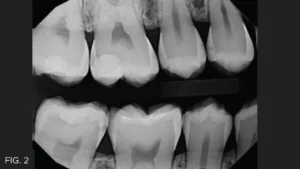

This clinical case highlights a common scenario. (FIG. 1) A Class II carious lesion was detected on the distal of #5. (FIG. 2) The patient was anesthetized via infiltration. Before preparation, a latex free rubber dam (True™ Dental Dam, Clinician’s Choice®) was placed to provide the first line of isolation.